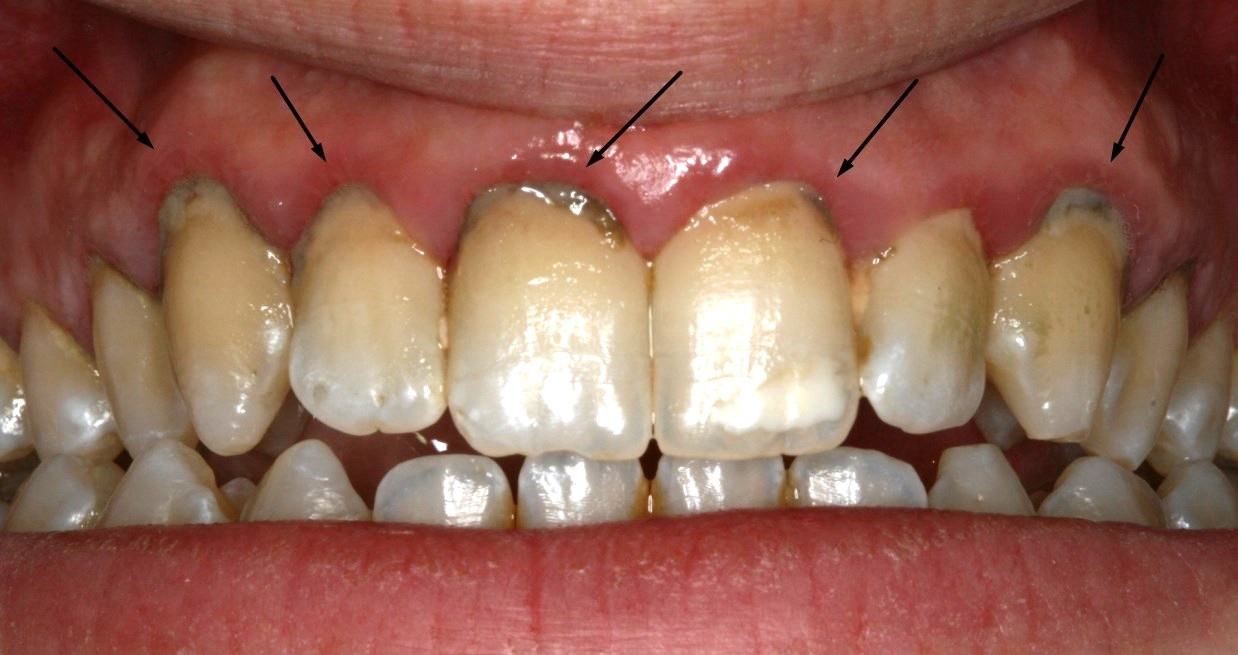

Έντονος ερεθισμός των ούλων από την παρουσία πέτρας και οδοντικής πλάκας

Μεγάλη συσσώρευση πλάκας και πέτρας έχουν προκαλέσει περιοδοντίτιδα